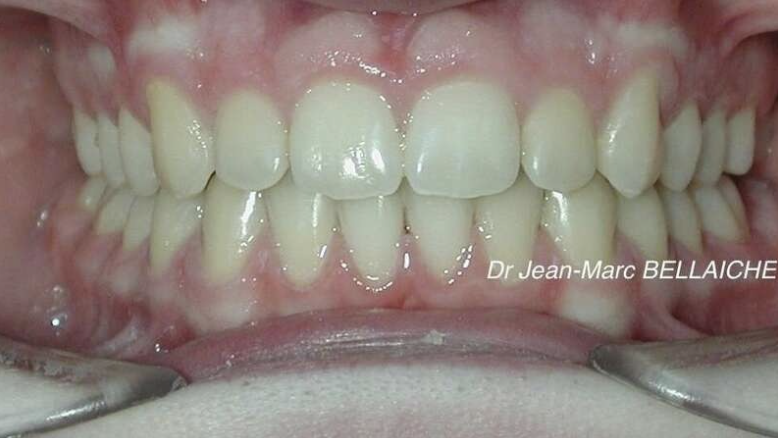

Cas 7 : Classe II avec encombrement sévère – Traitement sans extraction

Situation "Avant Traitement" : Classe II dentaire associée à un encombrement important de l’arcade supérieure, avec canines enclavées.

Cette jeune patiente présentait un très gros encombrement au maxillaire, rendant l’éruption des canines difficile. Après un diagnostic complet (photos, empreintes 3D, radio, examen du visage et endobuccal), un traitement sans extraction a été choisi. L’objectif était de mettre en place les canines tout en préservant l’équilibre des arcades. Un exemple de traitement conservateur possible même en présence d’un encombrement marqué.